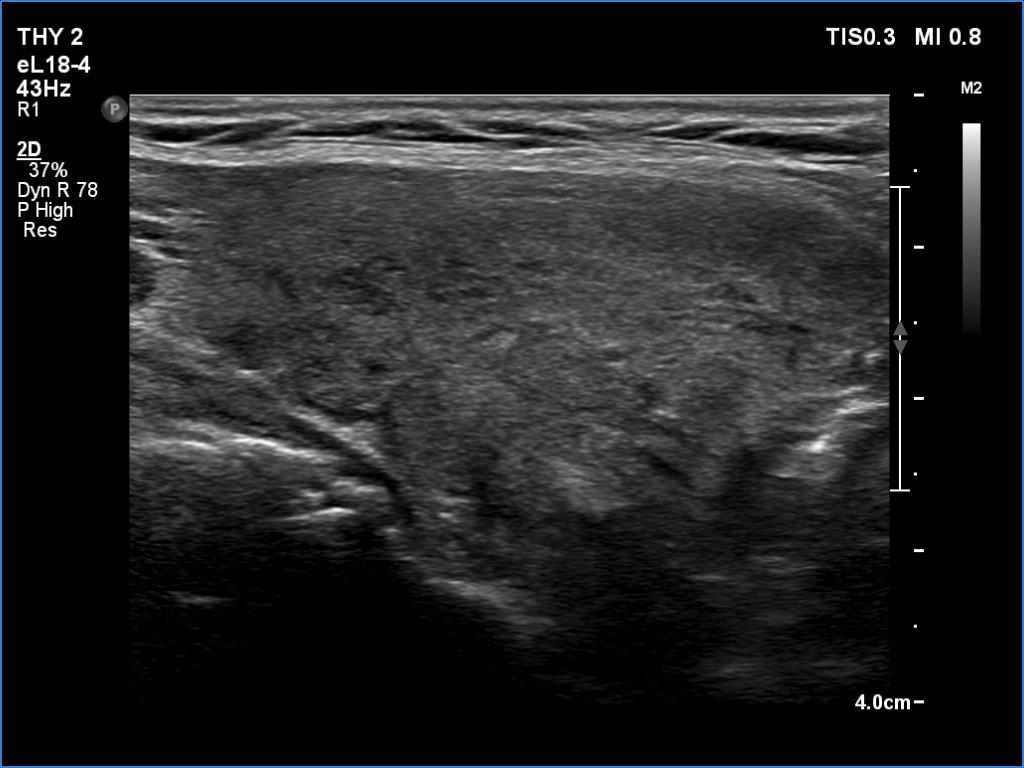

Clinical presentation: A 66-year-old woman was referred for cytology. The patient felt discomfort in her neck while lying on her left side for a few months.

Palpation: a firm nodule in the left lobe.

Diagnosis: Hashimoto's thyroiditis. Suspicion of follicular cancer.

Frozen section disclosed follicular cancer, therefore total thyroidectomy was performed. The definitive histopathological diagnosis was widely invasive follicular cancer and Hashimoto's thyroiditis.